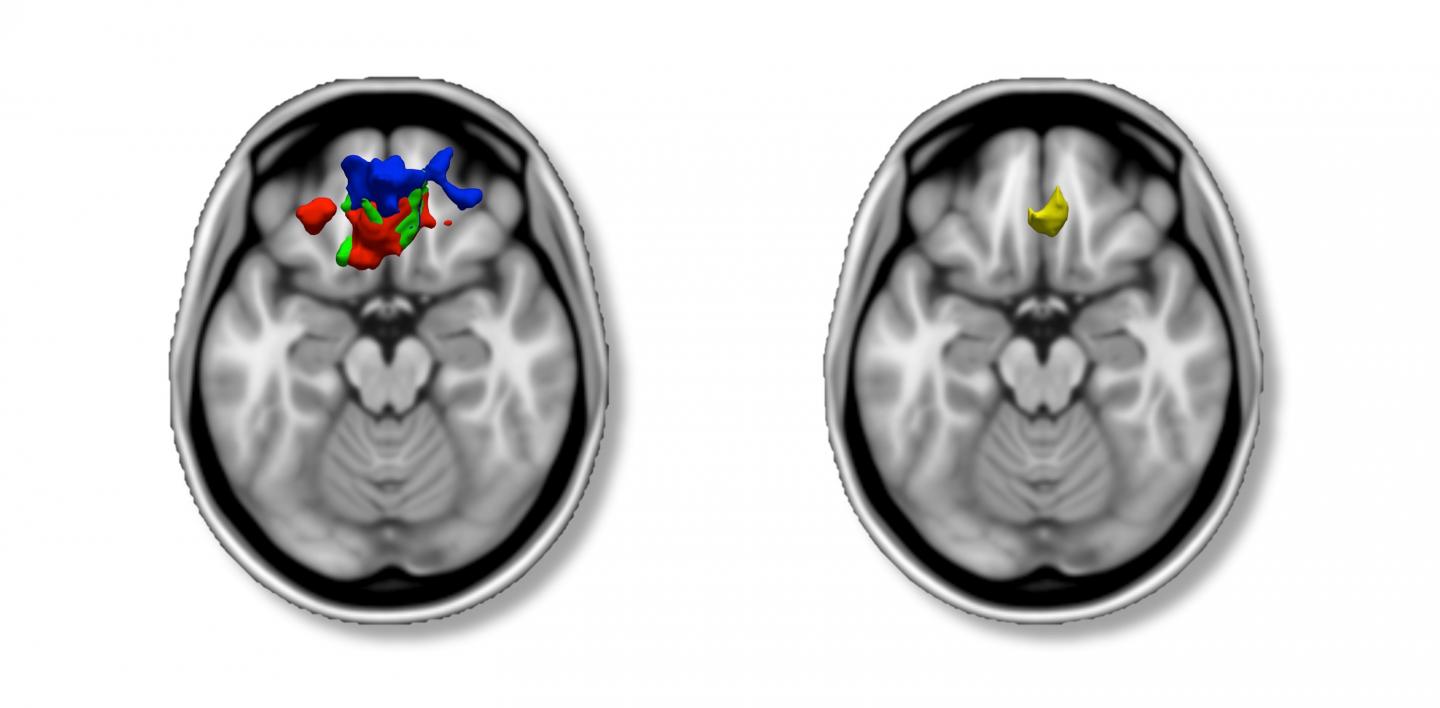

When they overlaid the imaging results from all of their analyses - using behavioral questionnaire data and symptom counts - they found an anatomical region of convergence; ADHD symptomatology reported by parents and adolescents was related to reduced gray matter volume in an area of the prefrontal cortex, the ventromedial prefrontal cortex (vmPFC). This relationship was particularly true for symptoms of inattention.

The team also found that this area of anatomical convergence was related to an objective behavioral measure of attention that has been previously associated with ADHD, reaction time variability. Past research by others has shown that ADHD youths exhibit more variability in their response times, and this is believed to reflect inattention and distractibility. Albaugh and colleagues found that greater variability in reaction time was associated with reduced volume in the the vmPFC.